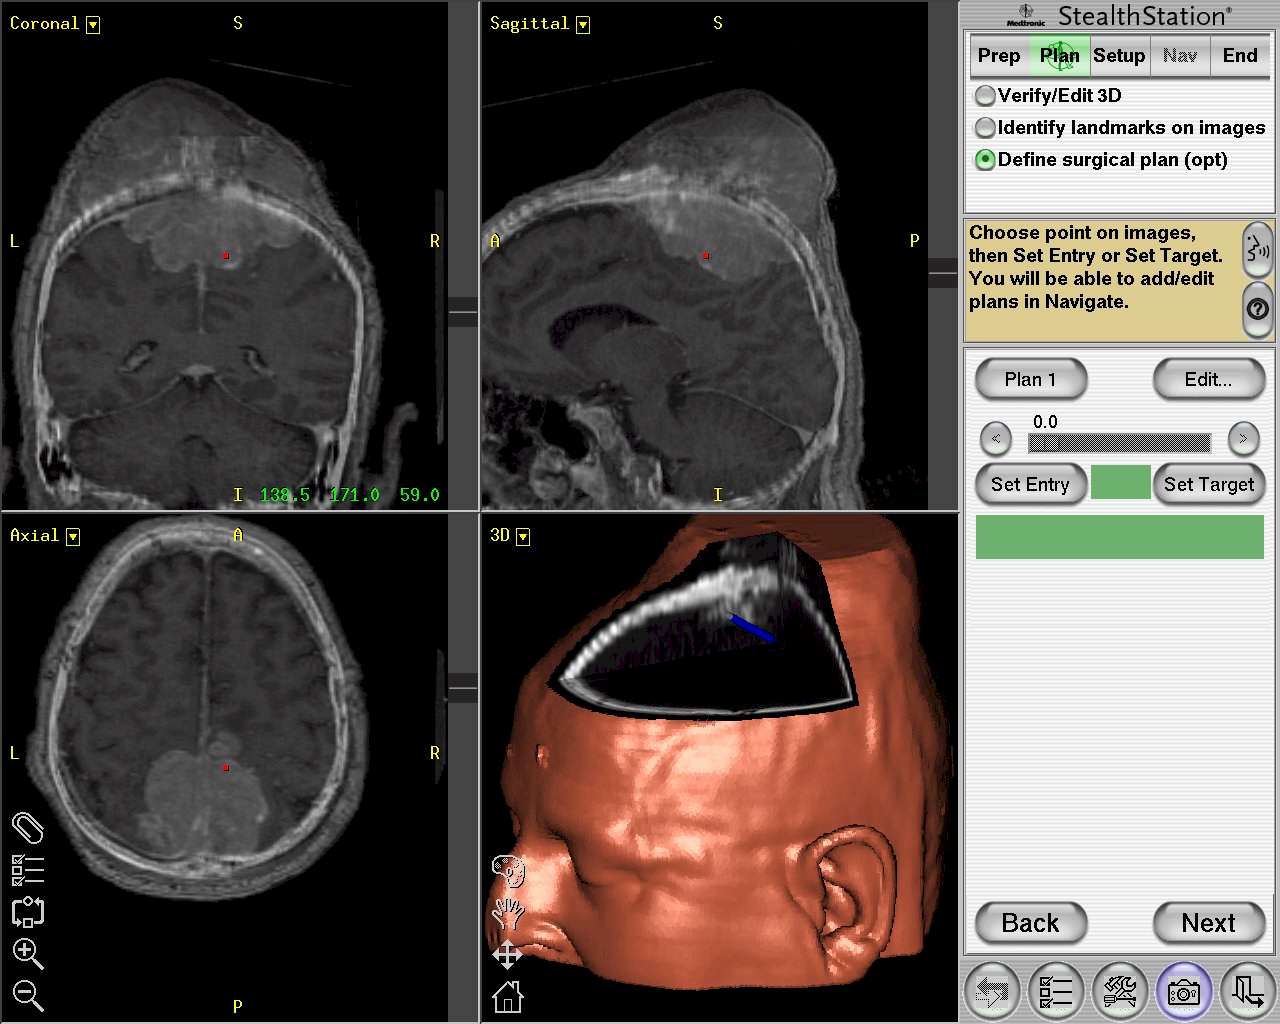

Prima di accedere alla sala il neurochirurgo ha l’abitudine di vagliare tutto, o in parte, il materiale neuroradiologico prodotto. Ultimamente è grandemente aiutato dall’uso routinario del neuronavigatore, la cui multiplanarità e la possibilità di realizzare piani di visualizzazione a varia profondità dalla superficie permette di progettare simulazioni mentali del planning chirurgico. Nell’impianto di cranioplastica tale elemento dai più non è ritenuto necessario, ma a nostro avviso non è così. Il neuronavigatore, grazie anche alla possibilità di sovrapporre la TC alla RM encefalica in un unico esame, permette agevolmente di capire come sia meglio condurre l’approccio chirurgico (Figura 1).

Figura

1. L'uso routinario del neuronavigatore è consigliato. Grazie

anche alla possibilità di sovrapporre immagini TC con quelle RM,

anche contemporaneamente. |